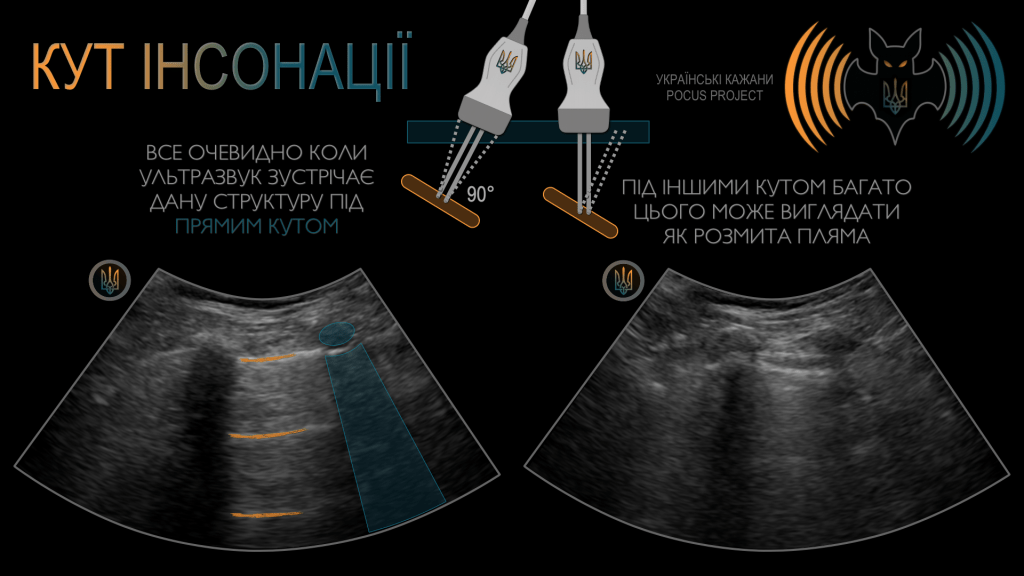

ПРИНЦИП №7: Найкраща візуалізація під кутом 90°; достатньо тиску та багато гелю. Читайте далі ➤

Найякісніші зображення отримуються, коли ультразвуковий промінь є перпендикулярним до досліджуваної структури. Для досягнення кута інсонації 90° може знадобитися змінити положення або нахил датчика на поверхні шкіри.

АНІЗОТРОПІЯ: це напрямкозалежний артефакт, за якого ехогенність структури змінюється залежно від кута інсонації, а не від властивостей самої тканини. Він виникає тоді, коли УЗ-промінь потрапляє на добре організовану структуру (наприклад, зв’язку, нерв або сухожилля) під кутом, що відхиляється від 90°. У результаті така структура може виглядати патологічно зміненою (гіпоехогенною), хоча насправді жодної патології немає. Після корекції кута інсонації зображення знову набуває нормального вигляду. Це поширена пастка в м’язово-скелетному POCUS і одна з основних причин хибнопозитивних діагнозів. У нашому прикладі місце прикріплення сухожилля чотириголового м’яза до надколінка незначно змінює напрямок і виглядає частково розірваним — доти, доки ми не відкоригуємо кут інсонації, гойдаючи датчиком.